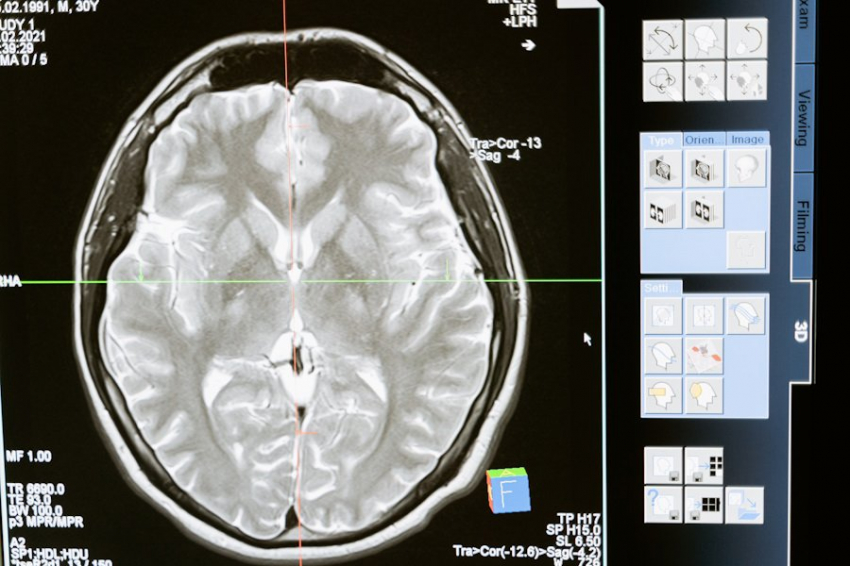

Фото из открытых источников

Новое исследование, проведенное учеными  King's College London, дало ошеломляющие результаты: древние вирусные элементы, интегрированные в ДНК человека, могут играть ключевую роль в развитии нейродегенеративных заболеваний, таких как рассеянный склероз (РС) и боковой амиотрофический склероз (БАС). Эти вирусы, называемые эндогенными ретровирусами человека (HERV), являются остатками древних инфекций, но, как выясняется, их активность не прекратилась миллионы лет назад.

Согласно порталу Science Direct, команда исследователей применила новейшие геномные технологии для выявления специфических вирусных последовательностей, которые могут повышать риск развития РС и БАС. Эти заболевания поражают центральную нервную систему, вызывая прогрессивную дегенерацию нейронов. Например, РС часто встречается у молодых людей, и в одной только Великобритании зарегистрировано более 150 000 случаев. БАС, хоть и встречается реже, отличается крайне тяжелым прогнозом.

Результаты исследования подтверждают, что вирусные элементы в нашем геноме могут влиять на функционирование мозга. Ученые обнаружили два специфических вирусных сигнатуры на хромосомах 12q14 и 1p36, которые связаны с риском БАС и РС. При этом, хотя другие нейродегенеративные заболевания, такие как болезнь Паркинсона и болезнь Альцгеймера, тоже были изучены, надежных вирусных сигнатур для них выявлено не было.